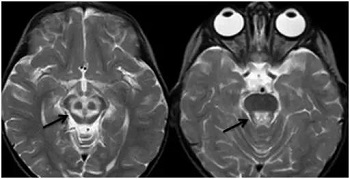

在查房的间隙,贾映海教授便在走廊里继续开讲起“走廊课堂”——“何谓熊猫征”来。贾映海教授说,“熊猫征”主要有“大熊猫脸征”和“小熊猫脸征”。其中,“大熊猫脸征”,红核在T2WI上呈现对称性的低信号,为大熊猫的眼,红核周围的内侧丘系、大脑脚上部、红核脊髓束及皮质脑干束神经纤维受累表现为T2高信号, 构成大熊猫脸上半部白色的轮廓;而双侧上丘、中脑导水管周围灰质神经核团正常的短T2信号及中脑导水管的长T2信号构成了大熊猫脸的下半部。

贾映海教授接着说,“小熊猫脸征”,中脑下部层面的双侧大脑脚、 上丘、 导水管、 导水管周围灰质核团、中央上核等构成了小熊猫脸的大体结构, 而双侧受累而呈长T2 信号的红核周围纤维束与短T2的中央被盖束勾勒出小熊猫的双眼。

贾映海教授说,熊猫征绝大多数为Wilson病(肝豆状核变性)的典型特征,也有个案报道见于Leigh病(亚急性坏死性脑脊髓病)。